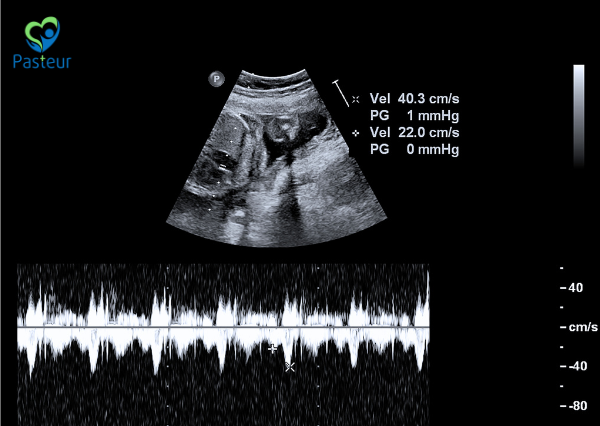

Siêu âm tim thai (fetal echocardiography) là phương pháp sử dụng sóng siêu âm để đánh giá cấu trúc và chức năng tim thai nhi. Nó cho phép bác sĩ theo dõi hoạt động của tim thai, bao gồm cách tim bơm máu, phát hiện các lỗ hổng, dị tật hoặc các vấn đề khác về tim.

- Siêu âm Doppler: Giúp đo lường luồng máu di chuyển trong tim và các mạch máu lớn, từ đó phát hiện các bất thường liên quan đến lưu lượng máu.